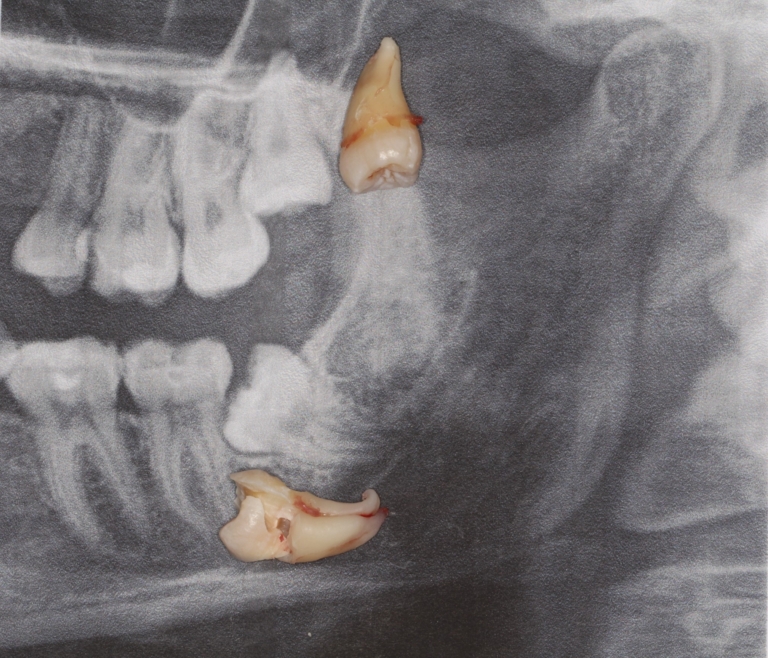

Pan Jarosław z Bytomia zgłosił się celem usunięcia ósemek. Pacjent okresowo borykał się z dolegliwościami związanymi z nawracającymi stanami zapalnymi dziąseł w okolicy zatrzymanych ósemek. Zabieg przeprowadzono w znieczuleniu miejscowym minimalnie inwazyjnie tj. atraumatycznie usunięto zatrzymane ósemki zaopatrując rany poekstrakcyjne odwirowanym osoczem Pacjenta (PRF). Mimo skomplikowania zabiegu wynikającego z zakrzywienia wierzchołków korzeni zębów oraz bardzo niekorzystnego położenia dolnej ósemki okres gojenia przebiegł spokojnie i bez powikłań.